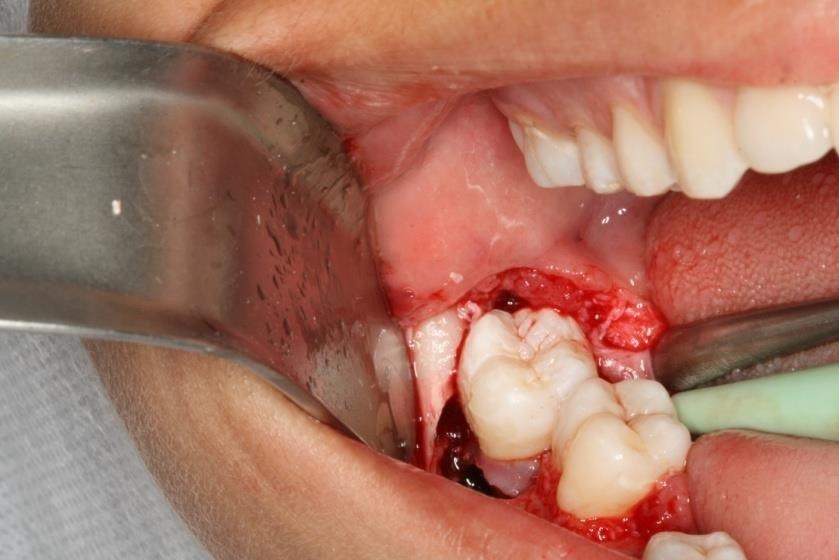

Técnica cirúrgica realizada em dois passos. Primeiramente, exodontia do elemento 46 (1° molar), curetagem do alvéolo para eliminar focos de infecção e preparação do alvéolo para o futuro transplante. (figura 2 e 3).

Após quinze dias foi feito a avaliação do alvéolo que receberá o dente transplantado, que neste caso não apresentou contraindicação para o procedimento. Feito a exodontia do 48 (3° molar) com o cuidado de não manipular as fibras do ligamento periodontal que são de suma importância para o sucesso do procedimento. (figura 4 e 5).

Figura 4 – Exodontia do elemento 48.

Figura 5 – retirada do elemento do alvéolo, mantendo o cuidado de não agredir as fibras do ligamento periodontal.